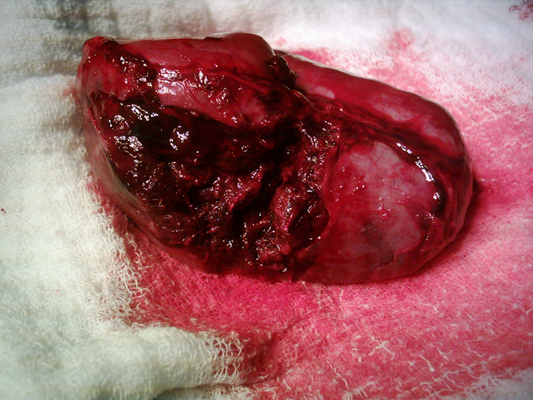

顱內血腫圖片

硬膜下血腫 (7)

硬膜下血腫 (8)

硬膜下血腫 (9)